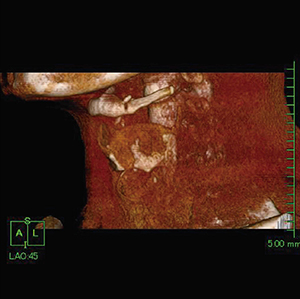

そこで,VR画像を用いて形態評価できないか検討を行った。喉頭軟骨はCT値が低く,骨化や石灰化を伴わない部分は筋肉などの軟部組織とほぼ同じ吸収値を示すため,閾値を変化させてもVR表示が難しく三次元画像として表示できなかった(図2)。

図2 喉頭部3D-CT画像

喉頭軟骨は軟骨組織とほぼ同等の吸収値となるため,三次元画像として表示できない。